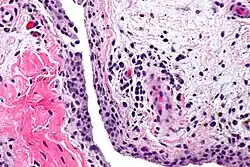

| Chronic synovitis | |

Synovitis is the medical term for inflammation of the synovial membrane. This membrane lines joints that possess cavities, known as synovial joints. The condition is usually painful, particularly when the joint is moved. The joint usually swells due to synovial fluid collection.

Medical Photographic Library